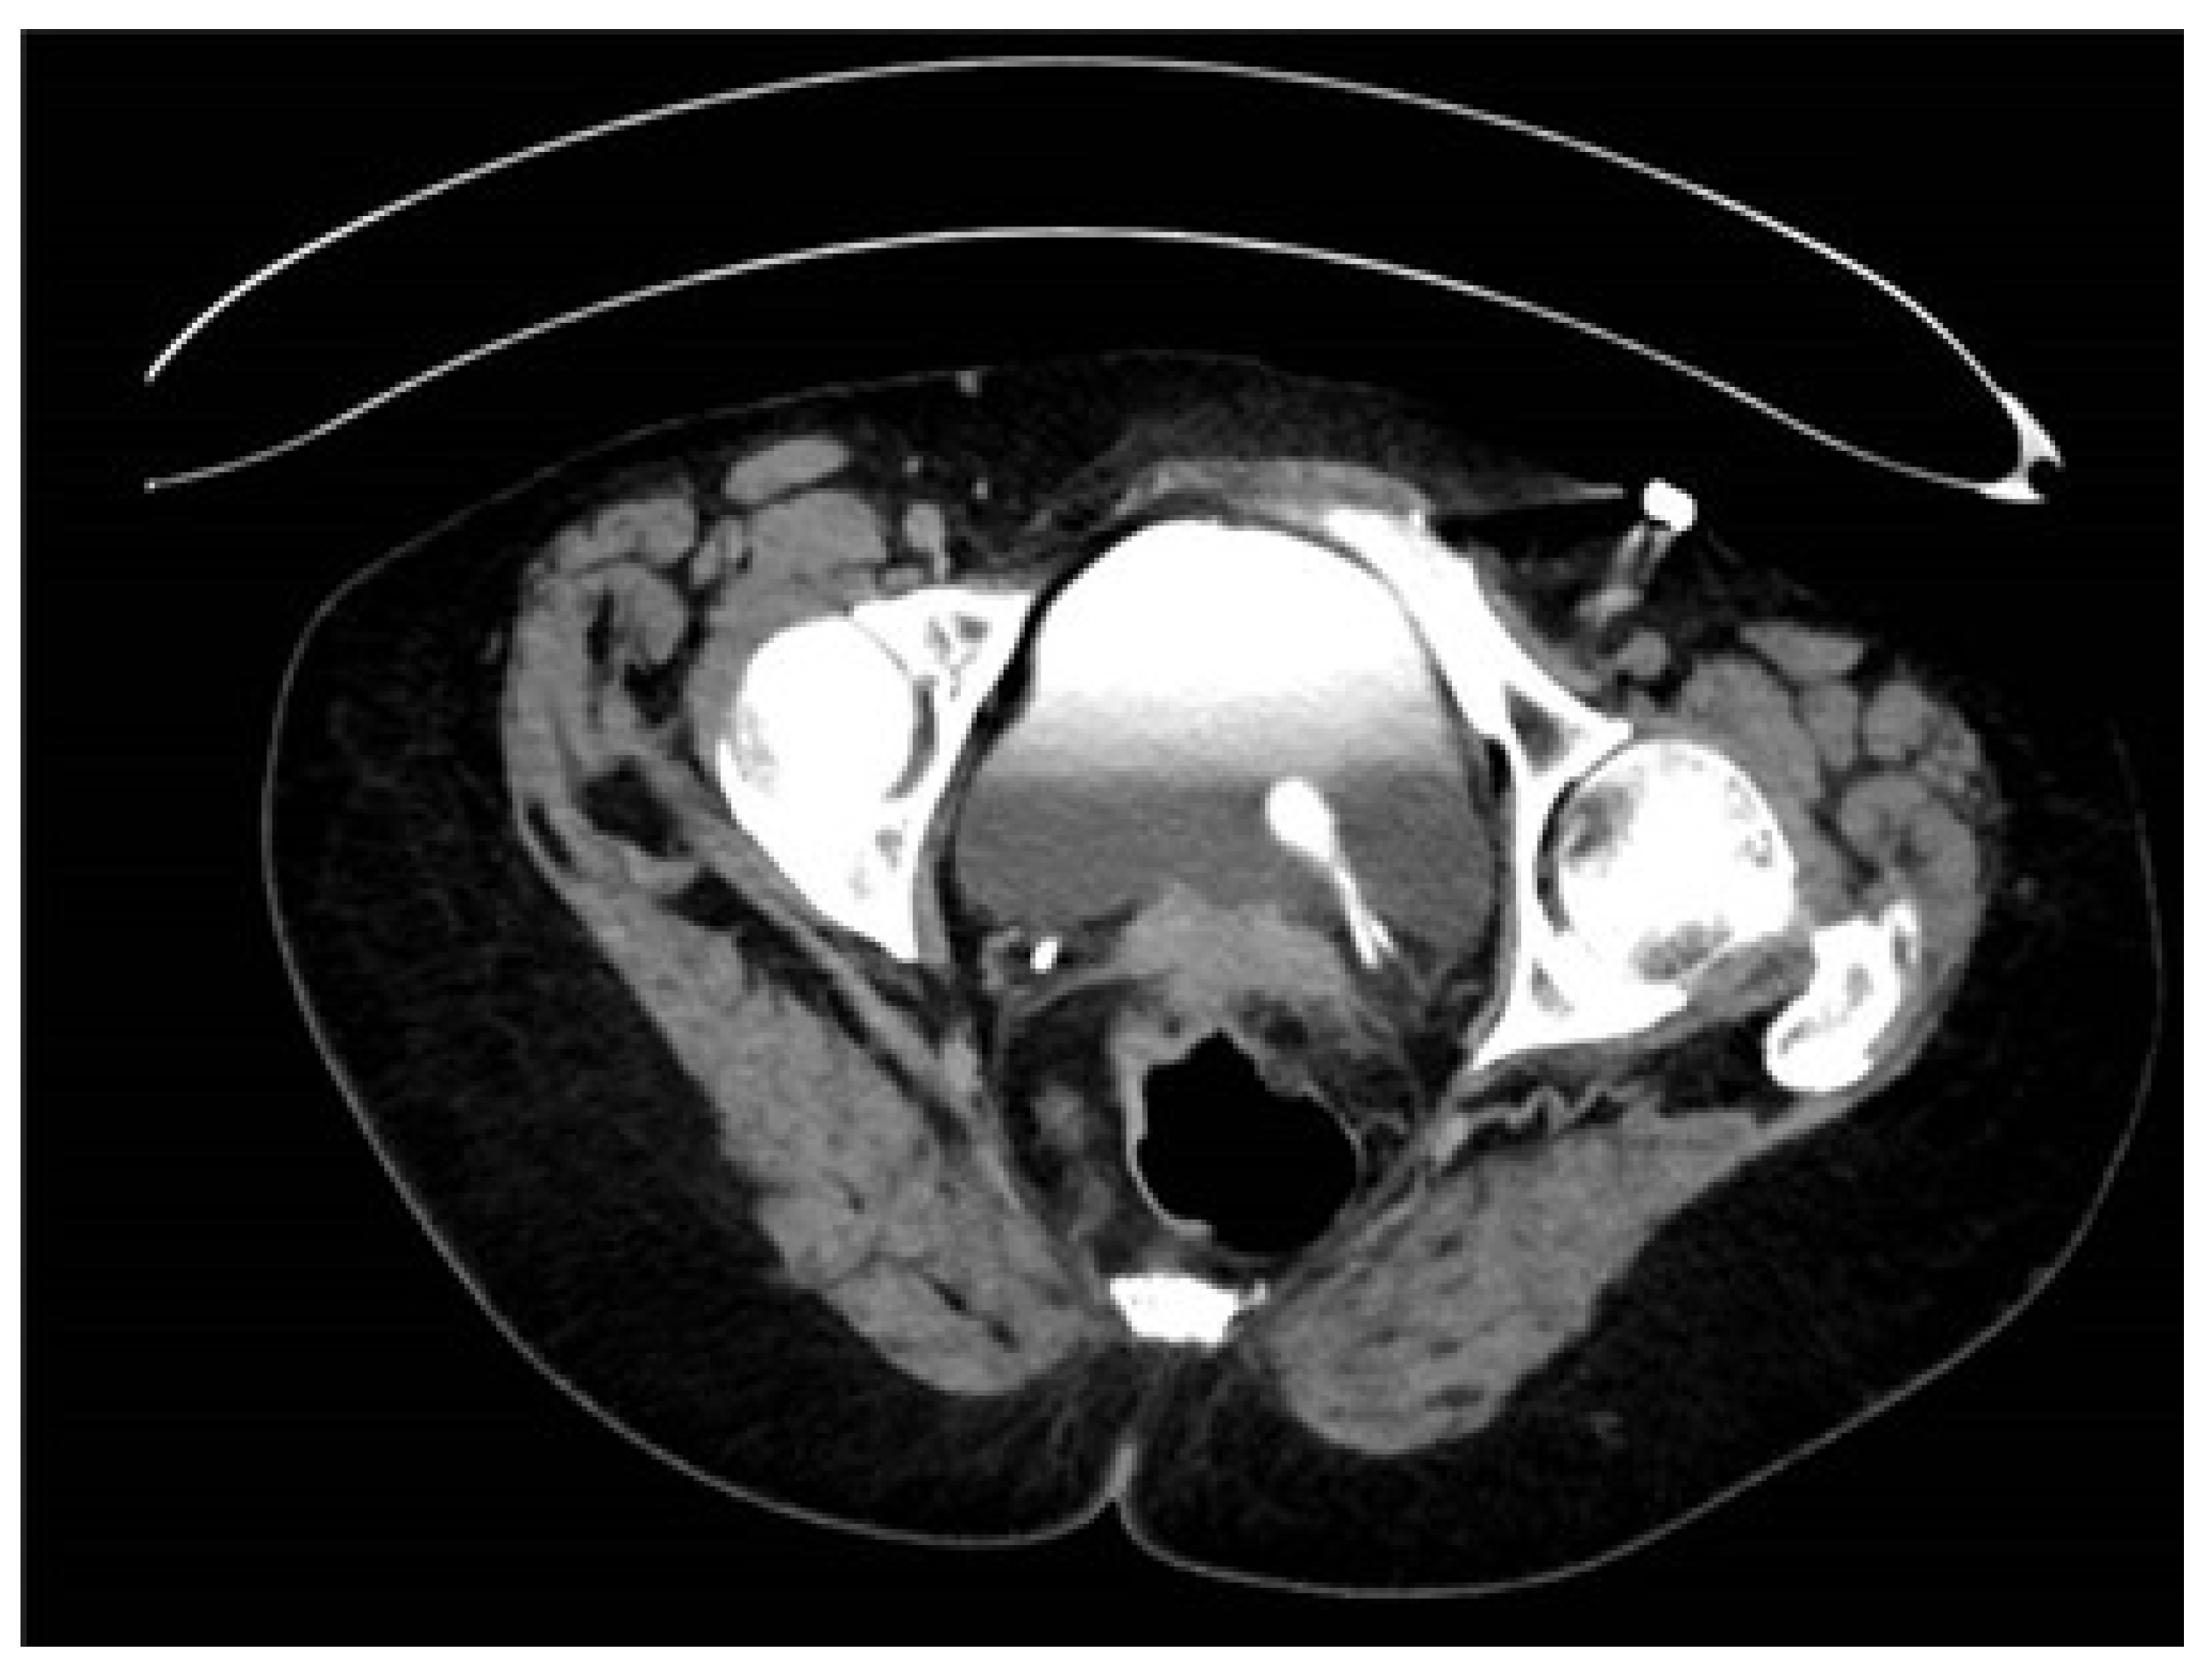

| 34 | Case presentation | 2023 | Israel | 69 | F | Hematuria | No per anamnesis | 0.8 | CTU, diagnostic URS | Complete | Left | Upper moiety renal pelvis | Upper pole Hemi-NU with distal common sheath ureterectomy, including bladder cuff, and reimplantation of the lower moiety ureter | Robotic assisted laparoscopic | Mucinous HG UC pT3NXM0 | Continued adjuvant therapy 9 months follow-up NED |